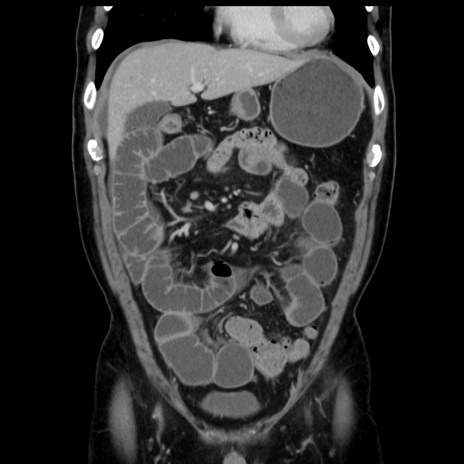

症例16(冠状断像)

【症例】 70歳代男性

【主訴】 腹痛、嘔吐

【現病歴】 約1ヶ月前より間欠的に腹痛と嘔吐あり、当院消化器内科を受診したところCTで多発する肝臓のLDAを指摘され、精査中であった。以降は消化器症状は安定していたが、2日前より嘔気と腹痛があり、同日より排便・排ガスが消失した。改善認めず、 本日、救急外来を受診した。

【既往歴】 大腸ポリープ切除後。

【身体所見】意識清明・会話良好、BT 36.3℃、BP 127/80mmHg、 P 80bpm、腹部:膨満あり、平坦・軟、上腹部正中および下腹部正中に圧痛あり、反跳痛なし、筋性防御なし。

【データ】WBC 7200、CRP 0.77